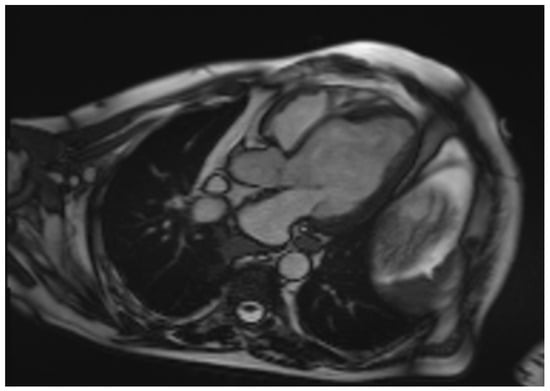

Cardiac sarcoidosis (CS) is a critical and frequently underdiagnosed phenotype of sarcoidosis, characterized by non-caseating granulomatous infiltration of the myocardium. This review synthesizes current knowledge regarding the pathogenesis, diagnosis, and management of CS. The disease manifests with a heterogeneous clinical spectrum ranging from asymptomatic conduction abnormalities to life-threatening ventricular arrhythmias and heart failure. Diagnosis remains challenging due to the patchy distribution of granulomas, which limits the sensitivity of endomyocardial biopsy. Consequently, a multimodal diagnostic approach is essential, integrating advanced imaging modalities such as cardiac magnetic resonance (CMR) with late gadolinium enhancement (LGE) and 18F-fluorodeoxyglucose positron emission tomography (FDG-PET). These tools not only facilitate detection but also enable the differentiation of active inflammation from chronic fibrosis. Histopathological assessment, supported by specific immunophenotyping and electron microscopy, remains the gold standard for confirming diagnosis and excluding mimics like giant cell myocarditis or infectious granulomatous diseases. Management requires a multidisciplinary strategy combining immunosuppressive therapy, primarily corticosteroids and steroid-sparing agents, with guideline-directed cardiac care, including implantable cardioverter-defibrillators for arrhythmia risk stratification. Emerging biomarkers and artificial intelligence-driven imaging analysis promise to further refine risk stratification and therapeutic monitoring, advancing precision medicine in this complex disorder. Full article

Show Figures

Figure 1